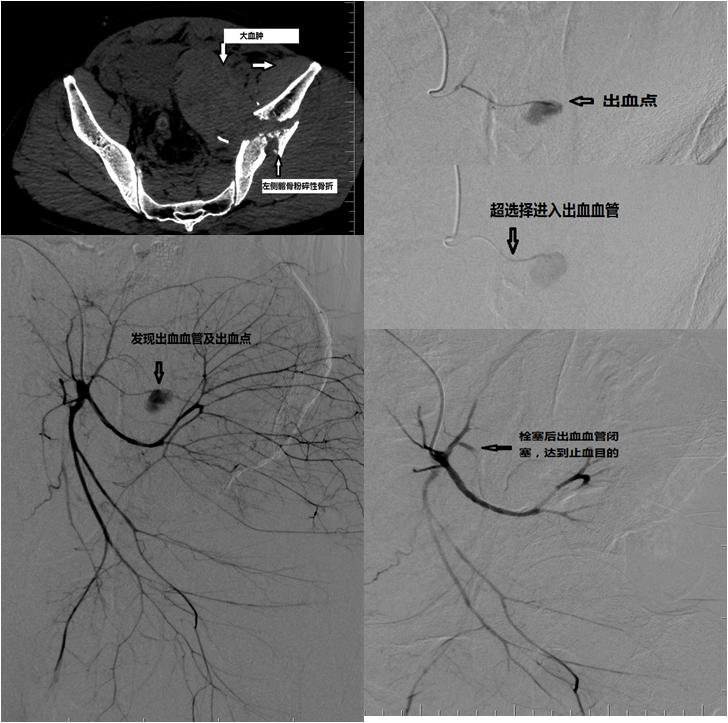

8月16日凌晨,一位50岁男性因高处坠落伤被收入聊城市二院,CT检查显示左侧髂骨、髋臼粉碎性骨折并腹盆腔血肿,失血性休克,血压80/55mmHg,心率150次/分,血常规检测血红蛋白持续降低。

在与患者家属充分沟通后,迅速启动介入急诊团队,包括肖纪涛主治医师、王彦哲护师、杨*武岳**护师、杨帆技师在内的介入团队成员 迅速赶到医院,到达介入诊疗室。在重症医学科张洪亮医师的监护下,立即为患者施行介入手术。术中使用DSA技术精准找到了损伤血管,证实腹盆腔巨大血肿形成的原因,并使用微导管超选择精准定位到出血的血管。医护人员迅速对出血的血管给予栓塞治疗,闭塞责任血管不再出血。观察40分钟后,再次DSA造影判断患者的血管情况,未见对比剂溢出。此时患者血压、心率、血氧饱和度等基本生命体征逐步好转,患者情绪趋向稳定, 尿道插管有黄色尿液排出,安全返回重症病房,接受进一步治疗。

“通俗地讲,我们使用的介入技术就利用穿刺针是在人体股动脉‘穿刺’一个口,将特定的导管利用这个穿刺口将导管沿血管送到人身体里各个部位,通过注入对比剂,进行血管造影,找到出血原因,并使用特殊的栓塞剂精准堵住出血血管的裂口,从而达到止血的目的。”肖纪涛主治医师介绍,经皮动脉介入DSA血管造影+选择性动脉栓塞术是治疗骨盆骨折导致大出血的高效手段,它既能精准定位出血血管,又能同时进行有效止血治疗,介入微创治疗也适用于人体其他部位外伤或肿瘤导致的血管损伤出血的治疗。